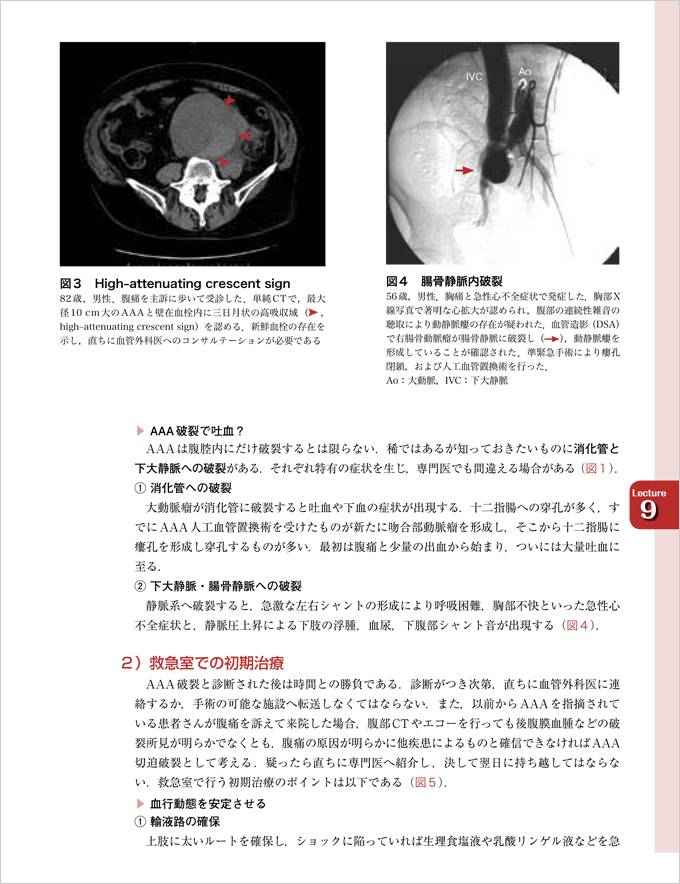

『Lecture9 軽快した腰痛! 失神! 胸部不快! でも…』より抜粋